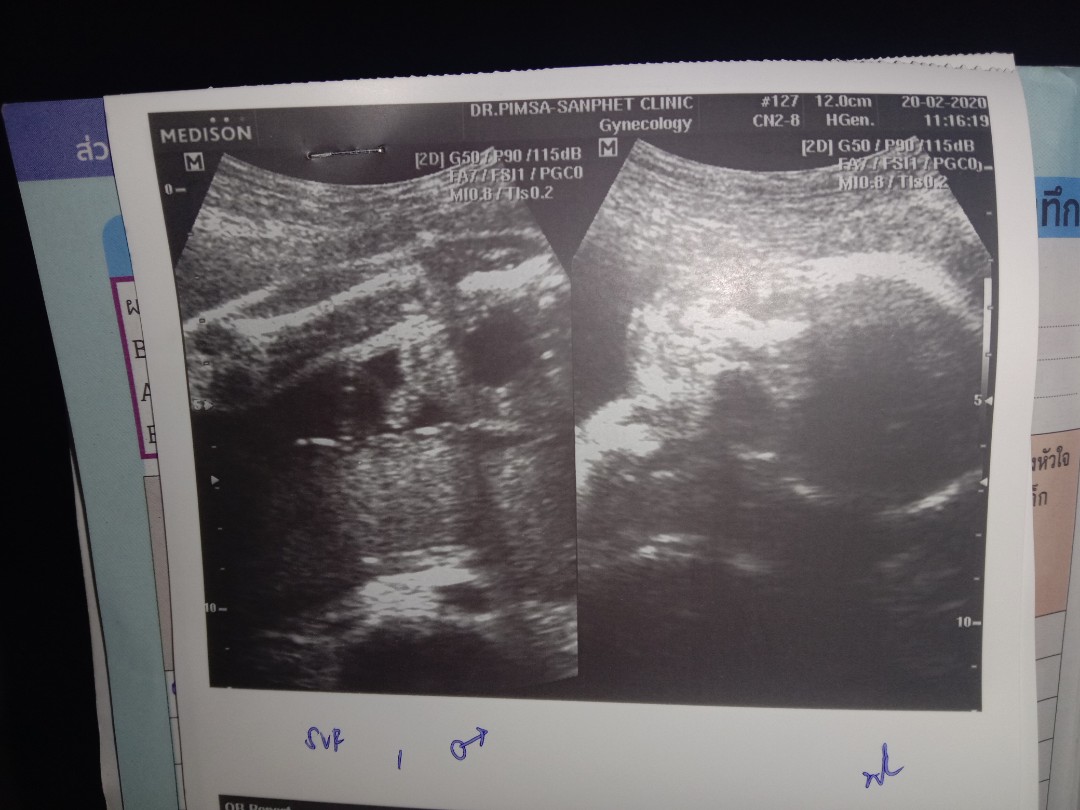

ขอดูใบซาวเด็ก ผช. ของแม่ๆ หน่อยค่ะ ?

ในภาพเป็น ผช ใช่ไหมค่ะ พอดีหมอขอชัวร์ๆ เดือนหน้า เลยสอบถามแม่ๆ ที่มีประสบการณ์ลูกชาย หน่อยค่ะ ?ขอดูใบอัตตลาซาวเด็ก ผช . หน่อยจร้าาา? ถาพไม่ชัดเพราะถ่าย VDO มาจร้า ??